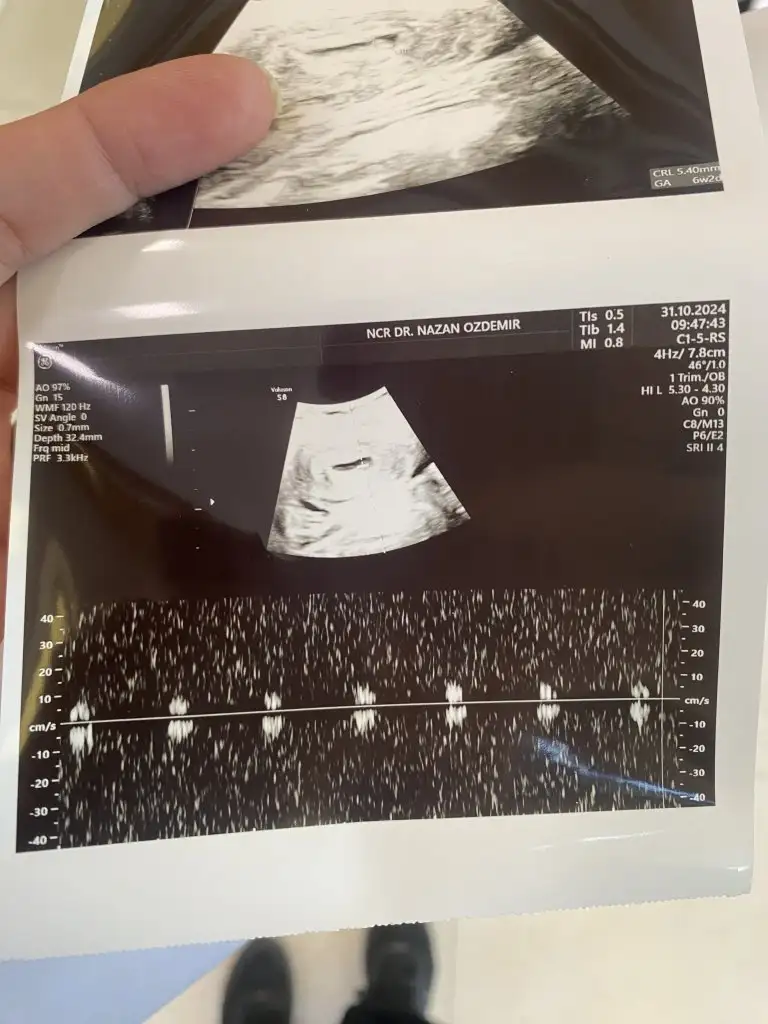

Benim için de tahminde bulunabilir misiniz cokk teşekkürler

Bugun gittim %90 kiz dediKız bence